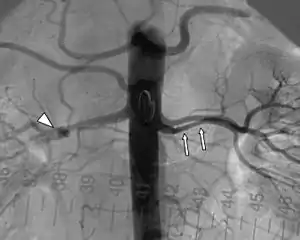

| پیکان مثلثی شکل یک آنوریسم را در سرخرگ کلیوی راست نشان میدهد. | |